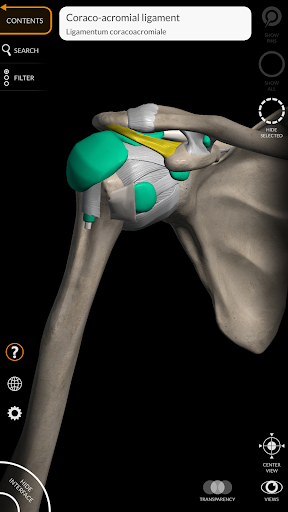

Các mô hình giải phẫu 3D đặc biệt chi tiết và có kết cấu lên đến độ phân giải 4k.

MÔ HÌNH GIẢI PHẪU 3D

• Hệ thống cơ xương

• Xoay và phóng to từng mô hình trong không gian 3D

• Tùy chọn ẩn hoặc cô lập một hoặc nhiều mô hình đã chọn

Các dây chằng được thêm